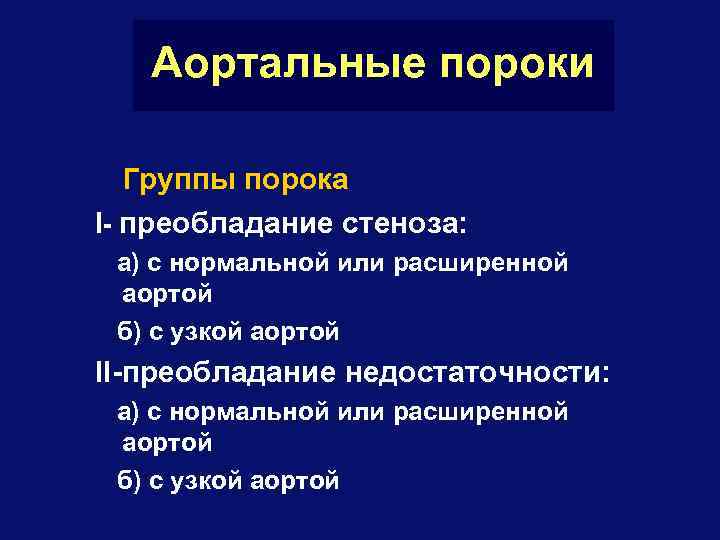

Аортальные пороки Группы порока I- преобладание стеноза: а) с нормальной или расширенной аортой б) с узкой аортой II-преобладание недостаточности: а) с нормальной или расширенной аортой б) с узкой аортой